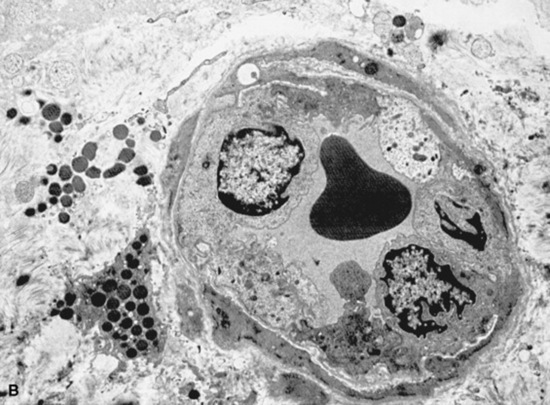

Ultrasound evaluation of horses with abdominal pain (colic) provides a rapid method to identify abnormalities within the gastrointestinal tract. Distention of the small intestine to a diameter greater than 5 cm has been strongly associated with strangulating or obstructing lesions19 (Fig. 32-11). In foals with intussusception, the small intestine appears enlarged and there is generally distended small intestine orad to the lesion; however, at the site of the intussusception there is a normal-appearing small intestinal wall (intussuscipiens) surrounded by a larger structure that appears to surround the inner small intestinal wall (called the intussusceptum)19 (Fig. 32-12). Large colon torsion occurs when the large colon rotates 360 degrees or more around the root of the mesentery to cause occlusion of venous drainage while maintaining arterial flow. This causes the wall to become thick and edematous. If ultrasound is performed in the cranioventral abdomen, just caudal to the xiphoid process, then a colon wall size greater than 9 mm is 100% specific for a large colon torsion21 (Fig. 32-13). A large colon displacement would have minimal to no vascular compromise, so it would be an ultrasound diagnosis based on exclusion. Chronic displacements did have a mild amount of edema in the colon wall, causing the size to be approximately 7 mm thick but never greater than 9 mm in the one study described.21 The colon and small intestinal wall will also become thick with inflammation. Small intestinal wall thickness greater than 4 mm is indicative of inflammation.19 The right dorsal colon can be imaged in the right tenth to twelfth intercostal space around the region of the costochondral junction, and a focal wall thickness of 9 to 12 mm has been identified with right dorsal colitis.23

image

Fig. 32-11 Transabdominal ultrasonographic image of a 6-year-old thoroughbred gelding with acute onset of colic. The small intestine is 7 cm in diameter and was noted to have minimal to no contractility. This is consistent for mechanical ileus. A strangulating lipoma was identified at surgery.

Courtesy of Cornell University.